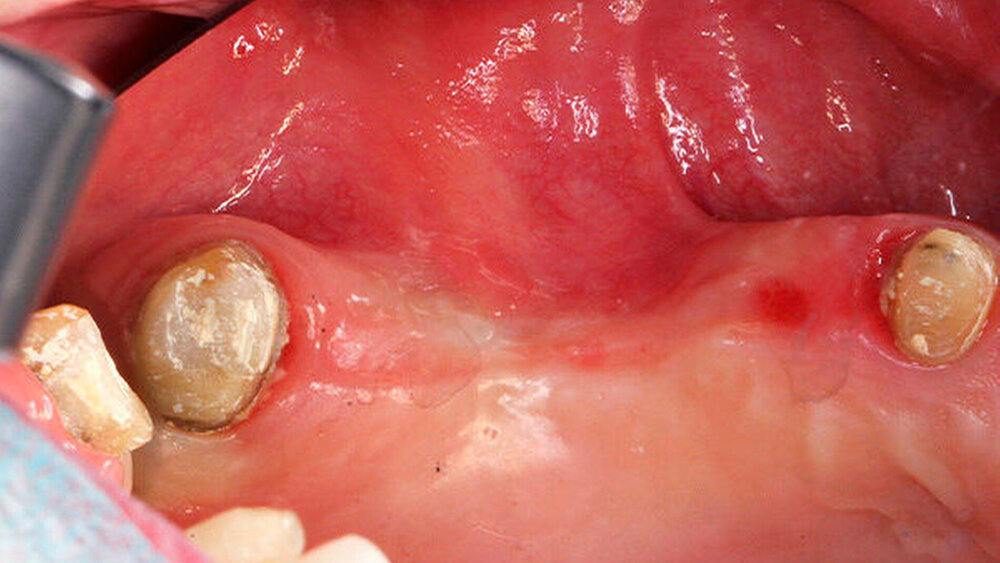

Die Schnittführung wurde nach dem Pillar-Sockel-Design (Blume) vorgenommen. Dabei liegt die Inzision weit im Vestibulum und verbindet zwei vertikale Entlastungsschnitte. Im Gegensatz zu der herkömmlichen krestalen Schnittführung bleibt das Periost über dem augmentierten Bereich damit völlig intakt. Nach der streng subperiostalen Präparation erfolgte die Kontrolle der Passung des CAD/CAM-Blocks. Ein ganz entscheidender Punkt ist, vor jeglichem Kontakt des Blockes mit Blut diesen in steriler Kochsalzlösung und am besten in der PRF-Flüssigkeit zu wässern, sodass sich keine Poren des Blocks mit Blutkoageln verschließen und innerhalb des Blocks ein nicht mit Blut gefüllter Hohlraum bildet. Vor der Befestigung des Blocks wurde die Kompakta des Empfängerbetts mit einer kleinen Kugelfräse mehrfach perforiert um sogenannte Bleeding Points zu setzen, die die Durchblutung des Knochenblocks gewährleisten. Mit zwei Osteosyntheseschrauben mit dem Durchmesser 1,5 mm und der Länge 9 mm wurde der allogene Knochenblock rotationssicher fixiert. Das Augmentat wurde mit einer dünnen Schweinepericard-Membran (Jason membrane, botiss biomaterials GmbH, Vertrieb Straumann) und der PRF-Membran abgedeckt. Der spannungsfreie Wundverschluss erfolgte mit der modifizierten vertikalen Matratzennaht nach Laurrell mit resorbierbarem Nahtmaterial (Vicryl 4.0). Postoperativ wurde ein Oberkiefer-DVT angefertigt. Die Nahtentfernung wurde im Rahmen der Nachsorgeuntersuchung sieben und 14 Tage postoperativ vorgenommen. Nach einer Heilzeit von sechs Monaten erfolgte die Implantation in Lokalanästhesie unter antibiotischer Abschirmung mit 2 g Amoxicillin oral eine Stunde präoperativ. Die Schnittführung erfolgte krestal, und nach subperiostaler Präparation wurde der Knochenblock dargestellt und die Osteosyntheseschrauben wurden entfernt. Danach wurden drei Implantate (Straumann) in den Knochenblock gesetzt und mit 0er-Verschlussschrauben abgedeckt. Die Wundrandadaptation erfolgte mit resorbierbarem Nahtmaterial, das bei der Verlaufskontrolle sieben Tage postoperativ vollständig entfernt wurde. Nach dreimonatiger gedeckter Einheilung wurden die Implantate im Rahmen einer Vestibulumplastik freigelegt. Dafür wurde eine erneute krestale Schnittführung regio 14 bis 17 vorgenommen und ein Splitflap präpariert. Der vestibuläre Wundrand wurde mit Einzelknopfnähten im Vestibulum fixiert. Im Bereich der Implantate wurde der Splitflap perforiert, um die Abdeckschrauben gegen Gingivaformer auszutauschen, und der Bereich des nun freiliegenden Bindegewebes wurde mit einer 3D-vernetzten Kollagenmatrix (mucoderm, botiss biomaterials GmbH, Vertrieb Straumann) abgedeckt. Diese wurde zunächst gewässert, um die Verarbeitung zu erleichtern, und an den Stellen der Gingivaformer gestanzt. Die Nahtentfernung erfolgte neun Tage postoperativ. (Abb. 1a bis 1f).

Ein 29-jähriger Patient stellte sich mit einer massiven Alveolarkammatrophie im rechten Unterkiefer in unserer Praxis vor. Diese lag in langen Jahren der Zahnlosigkeit begründet. Eine Beckenkammaugmentation kam für den Patienten nicht in Betracht. Dennoch wünschte er die Versorgung mit festsitzendem Zahnersatz. Nach ausführlicher Beratung entschied sich auch dieser Patient für eine Augmentation mit einem patientenindividualisierten allogenen CAD/CAM-gefertigten Knochenblock. Die DICOM-Daten des Unterkiefer-DVTs wurde an die Firma Zimmer gesendet, und es erfolgten wie im oben beschriebenen Fall eine virtuelle Planung und das virtuelle Design des allogenen Knochenblocks anhand der geplanten Implantatpositionen. Nach der üblichen Kontrolle und Freigabe des Chirurgen erfolgte die eigentliche Fertigung und Übersendung des Knochenblocks in die Praxis. Die Augmentation erfolgte auch in diesem Fall in Vollnarkose unter antibiotischer Abschirmung perioperativ mit Ampicillin. Die Schnittführung im Unterkiefer unterscheidet sich von der Sockelschnittführung im Oberkiefer aufgrund der Anatomie (N. mentalis). Auch bei diesem Patienten wurde eine tief im Vestibulum liegende bogenförmige Inzi‧sion durchgeführt, jedoch ohne die vertikalen Entlastungen. Nach streng subperiostaler Präparation erfolgte die Darstellung des N. mentalis. Die Vorbereitung des Spenderbetts sowie die Wässerung, Einpassung und Befestigung des allogenen Knochenblocks gestalteten sich wie im Fallbeispiel 1. Die Heilzeit des Knochenblocks dauerte ebenfalls sechs Monate. Zwei Implantate (Straumann) wurden nach krestaler Schnittführung in Lokalanästhesie eingebracht und heilten subgingival binnen drei Monaten ein. Aufgrund des massiven Volumenzuwachses war auch ebenfalls eine Vestibulumplastik im Zuge der Implantatfreilegung notwendig. Das Prozedere verlief ebenfalls wie im Fallbeispiel 1. Das freiliegende Gewebe wurde mit einer Kollagenmatrix abgedeckt. Dadurch konnte die Breite der befestigten Gingiva deutlich verbreitert werden.